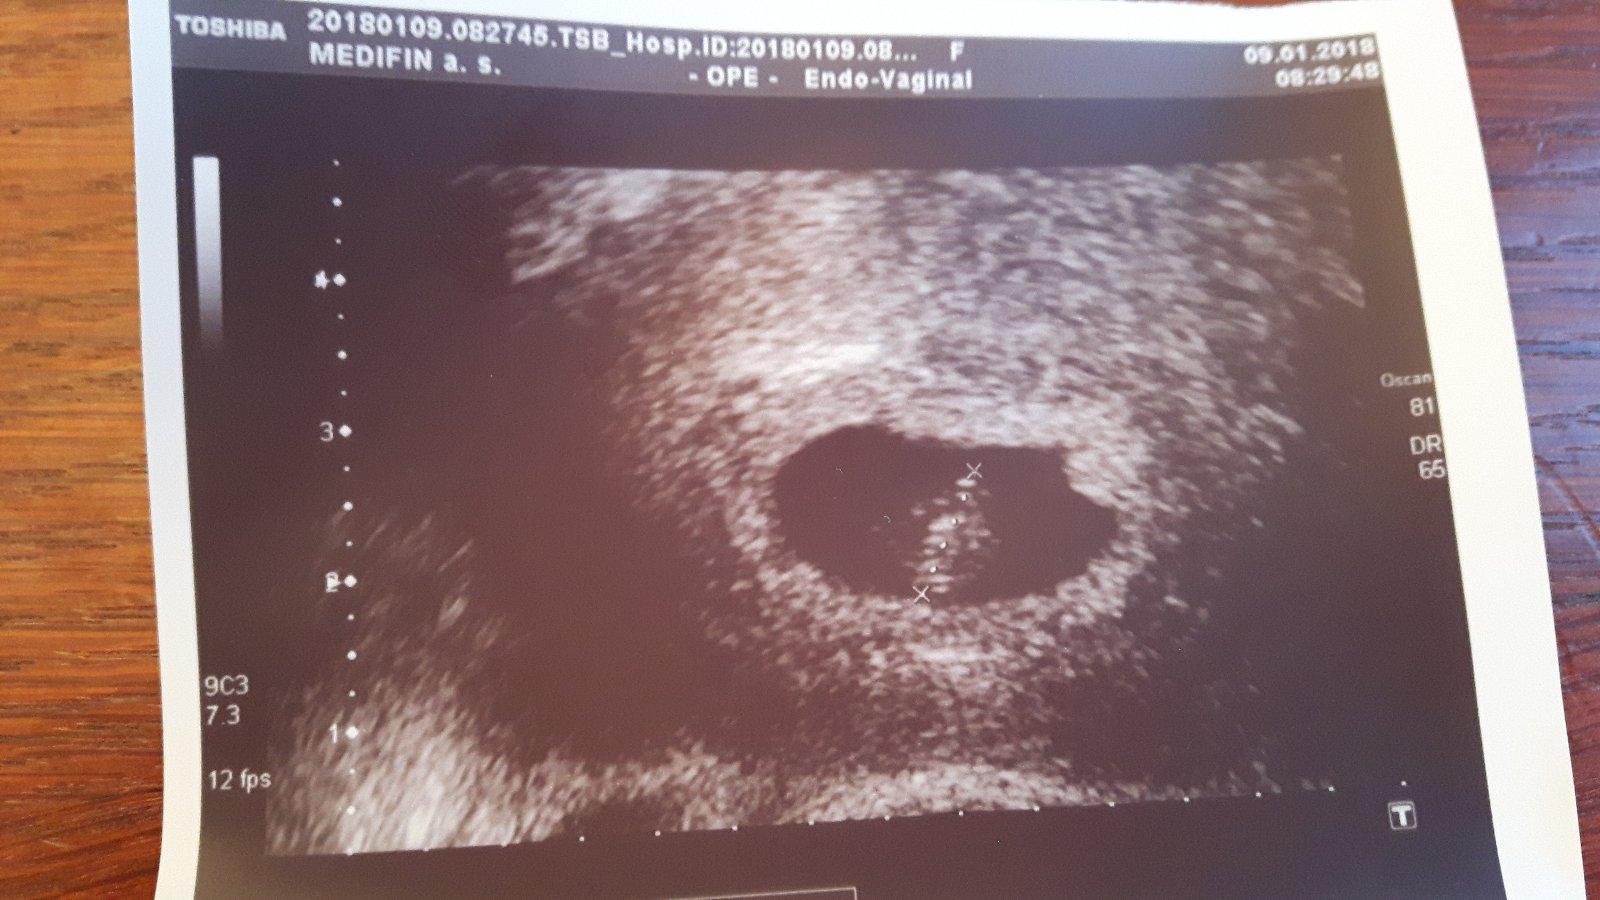

Chtěla jsem se zeptat, zda někdo někdy řešil něco podobného, jakoale změnu caru nebo stížnost. Od začátku jsem měla pocit, že je něco špatně. Opakovaně jsem volala do caru, že hcg roste velice pomalu, zda mohu k nim přijít na kontrolu. Vždy jsem byla odbytá, že opakovat odběry hcg jsou zbytečné, vše je v pořádku a já se mám hlavně uklidnit. V úterý mi dokonce sestra řekla, že vzhledem ke špatně rostoucímu hcg se o mimodelozni těhotenství jednat nemůže.kontrolu jsem dostala až za dva týdny. Ze zoufalství jsem ve středu začala vše řešit se svým gynekologem, který měl úplně jiný názor a v pátek pak musela akutně na operaci, jelikož mi vejcovod praskl. Chápu že nikdo nemůže za to, kde se embryo uhnizdi, ale přístup v caru mi rozhodně v pořádku nepřipadá. Řešil by to někdo zněkdy vasna stížností, nebo to mám přejít a nechat být... Děkuji za názory🍀